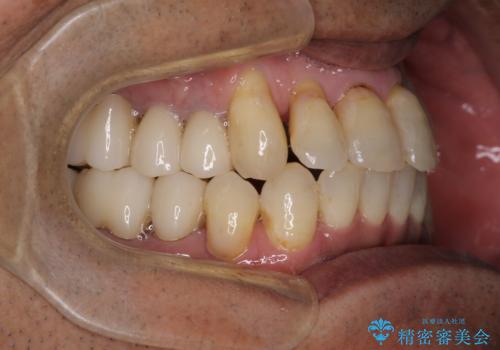

歯槽骨の再生治療を行ったため、外科処置後の静置期間がながくなり、4年弱の治療期間となりました。

初診来院時には矯正治療を行うことは想像していなかったようで、治療後には咬みやすさだけでなく、前歯が大変審美的に仕上がり、患者様には大変満足していただきました。